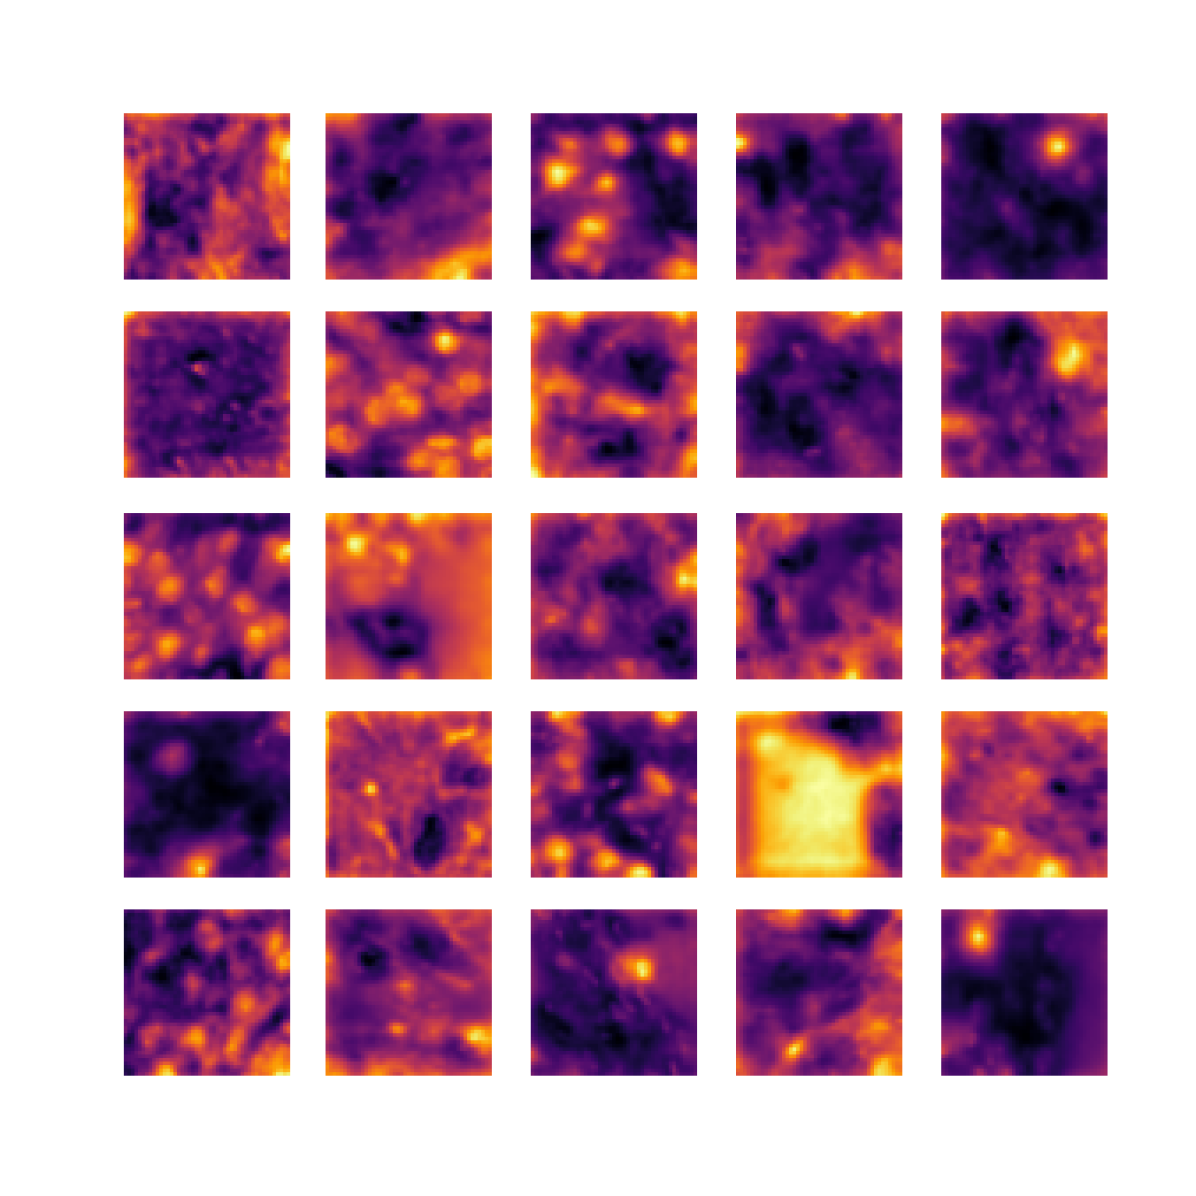

We also analyse the activation maps for each model using GradCAM as described in section S3. This offers more insight into the areas of the image which are contributing most heavily to the models’ representations. In Figure 4(b) we present some representative examples, however, a larger selection which was chosen at random is presented in Figures S10 to S25. The larger selection makes it easier to see the emergent patterns, including that privileged Siamese models tend to mainly identify features which are strongly present in both inputs, while unprivileged Siamese models tend to learn more diffuse features that are not specific to one cell phenotype or image region. TriDeNT ♆ incorporates both sets of features, learning both features specific to the privileged data and more the general features associated with unprivileged Siamese networks.

We can see in Figure 4(b) panel A that for ERG, the privileged Siamese model focuses almost exclusively on any nuclei which could be endothelial cells. As there are very few endothelial cells in the dataset, it could be an effective strategy to identify anything that could potentially be an endothelial cell to minimise the difference between the representations of the H&E model and the IF mask model. In the corresponding unprivileged Siamese image, we see that the model identifies some of these nuclei, albeit less strongly, but also focuses heavily on the other tissue and even the background, while strongly fixating on two spots of debris in the center of the image. This model has less ‘incentive’ to learn the weak features related to endothelial cells as these occur rarely and are not easy to detect, while more generic strong features such as the presence of connective tissue and the prevalence of background are more common and predictable from augmented images. We see that TriDeNT ♆ combines these two feature sets, strongly identifying nuclei while also identifying the connective tissue.

In panel C we see a similar pattern, with the privileged Siamese model fixating solely on the nuclei, while the TriDeNT ♆ model takes a more balanced approach. The unprivileged Siamese model appears to focus on a single cluster of nuclei while neglecting others, and similarly identifies an area of fibroblasts with its distinctive pattern but does not others.

In contrast to panels A and C which represent models with poor privileged Siamese results, panels B and D represent models whose privileged Siamese results were comparable to both TriDeNT ♆ and even the supervised baseline. It is therefore interesting to note that there are far more similarities between the privileged Siamese and TriDeNT ♆ models in both cases. Particularly in panel B, TriDeNT ♆ and the privileged Siamese model return virtually identical heatmaps, with both strongly identifying epithelial nuclei and neglecting the same areas of connective tissue. The unprivileged model in this case appears to focus solely on the centre of the image, giving a significantly different heatmap to the other panels.

Panel D again shows the previous pattern, with the privileged Siamese model identifying the features strongly present in the privileged data – fibroblasts – while neglecting the nuclei present. TriDeNT ♆ also strongly identifies the connective tissue, but, unlike the privileged Siamese model, does not completely neglect the nuclei. The unprivileged Siamese model primarily identifies background, and does not appear to identify the nuclei in this example.